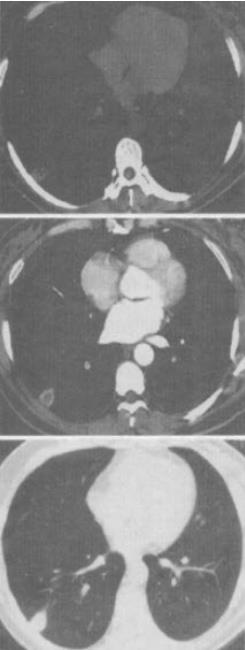

- 单项选择题 男,43岁,右胸背痛13天,ESR:15mm/小时,CT检查如图,最可能的CT诊断为()。

A、肺脓疡

B、周围型肺癌

C、炎性假瘤

D、肺结核

E、错构瘤

- A